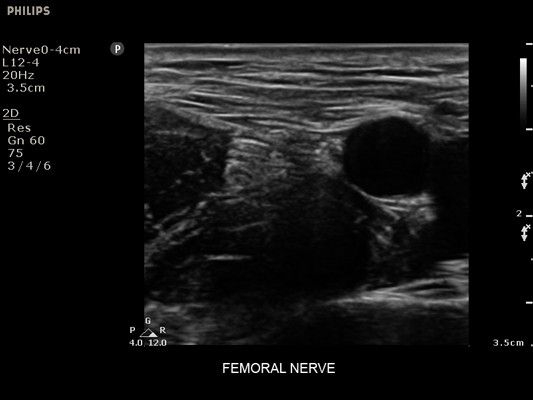

• Метки центральной линии на датчиках L12-4 и C6-2 для упрощения внеплоскостной навигации

• Сосудистый доступ

• Диагностика нервов

• Линейный УЗИ датчик Philips L12-4